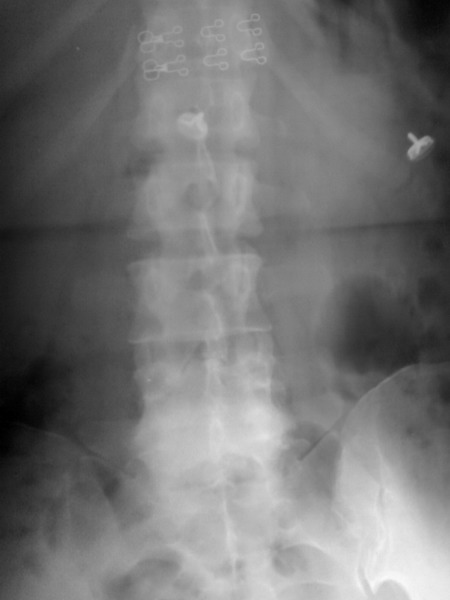

以下是引用zhangzhongshou在2008-7-31 22:22:00的发言:[br]腰4双侧椎弓峡部崩裂,ii度前滑脱,继发性椎管狭窄。伴腰4-5椎间盘退行性变。

以下是引用99重阳在2008-7-31 21:19:00的发言:[br]腰4椎体向前滑脱